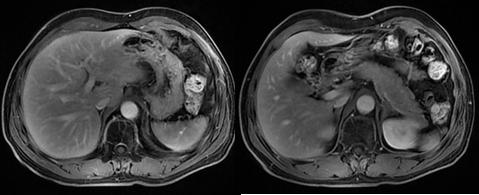

MR示肝脏转移较前有所增大(2020.11)

MR示经过放疗病灶基本消失(2021.)